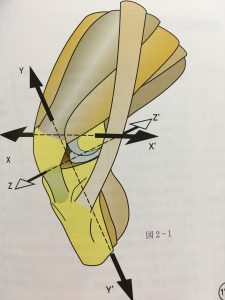

少し複雑な図になりますが、膝の曲げ伸ばしをする時の軸は「X」です。

この軸が平行に保つことができれば曲げ伸ばしもスムーズなのですが、ガニ股のような形をした脚ですと軸が外側にずれてしまいます。